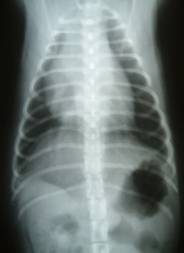

- 門脈大静脈短絡|X線検査にて疑うことができる

-

- 肝臓が縮小時に腎臓が拡大

- 側面像では正常の胃は肋骨に沿うが肝臓の縮小があると胃が頭側変位する背腹像では胃が横隔膜に近づく